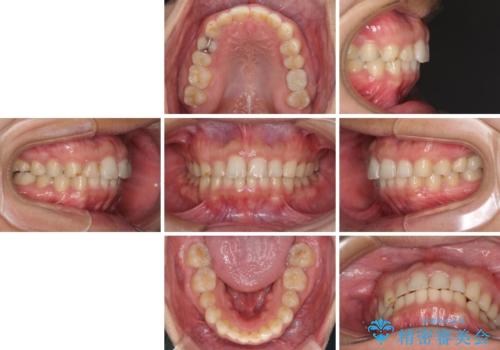

矯正治療とインプラント治療を同じ歯科医師が担当することで、通常見られるような複数医院を行き来する煩雑さや、複数担当医の見解の違いによる治療の遅滞といった煩わしさは一切なく、スムーズに治療を進めることができました。

安定して咬めるようになり、患者様には大変満足していただきました。